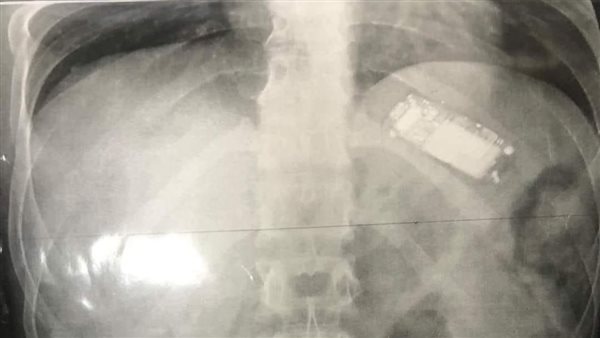

ابتلعه منذ شهرين.. استخراج تليفون محمول من بطن شاب بالمنصورة

نجح فريق طبي بـ مستشفي الباطنة التخصصي جامعة المنصورة، وبقيادة الدكتورة أسماء جميل مدرس واستشاري الجهاز الهضمي والمناظير بجامعة المنصورة، من استخراج موبايل من معدة شاب كان قد ابتلعه منذ شهرين، وذلك بعد عدة محاولات لاستخراجه وباءت بالفشل.

من جانبها، صرحت الدكتورة أسماء جميل، مدرس واستشاري الجهاز الهضمي والمناظير، بأنهم استطاعوا استخراج التليفون المحمول من معدة الشاب دون إجراء جراحة، ولكن عن طريق منظار طبي، حيث أن الأطباء كانوا قد حاولوا من قبل استخراجه، لكنهم لم يتمكنوا من ذلك.

وأضافت الدكتورة أسماء في تصريحات خاصة لـ القاهرة 24، أنهم استخرجوا التليفون المحمول من معدة الشاب، أمس الاثنين، مشيرة إلى أنها كانت المحاولة الأخيرة لاستخراج الموبايل دون جراحة عن طريق المنظار، وذلك قبل تحويله إلى قسم الجراحة لاستخراج الموبايل من معدته.

وأوضحت الدكتورة أسماء، أن صعوبة استخراج الموبايل عن طريق المنظار الطبي؛ تمثلت في كبر حجمه، منوهة بأنه عندما أخرجوا الهاتف من معدة الشاب؛ وجدوه من ماركة نوكيا.

واختتمت الدكتورة أسماء حديثها مع القاهرة 24، قائلة: الشاب قد ابتلع الموبايل من شهرين، وحاول إخراجه لكنه لم يتمكن بسبب كبر حجمه، وبعد قضاء كل تلك الفترة وهو محتفظ بالموبايل في المعدة؛ أثر ذلك عليه وألحق الضرر به، مما دفعه للجوء إلى الأطباء لاستخراجه، ونجحنا في النهاية بإجراء الجراحة واستخراجه.